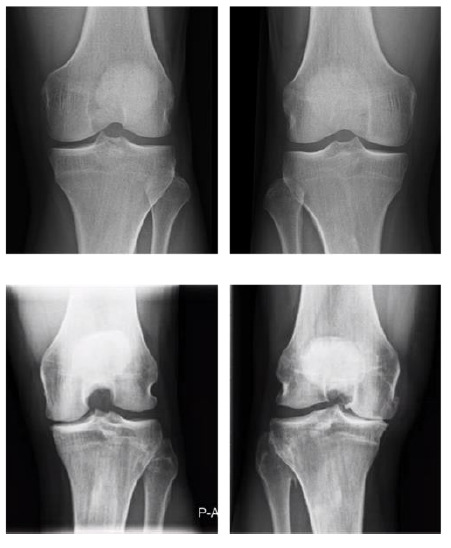

Background: Knee osteoarthritis (OA) is common amongst retired male professional footballers. There is limited understanding with respect to the interplay between imaging findings, clinical presentation and patient-reported outcome measures (PROMs) in retired professional footballers with knee OA.

Objectives: This pilot study aimed to evaluate the extent of radiological and clinical knee OA in a cohort of retired male professional footballers, and to explore the relationship between these findings and knee-related PROMs.

Methods: Fifteen retired male professional footballers underwent knee radiographs and were surveyed on their history of clinical OA, severe knee injury and previous knee surgery. The Knee Injury and Osteoarthritis Outcome Score Physical Function Short Form (KOOS-PS) and the Patient-Reported Outcomes Measurement Information System Global Health (PROMIS-GH) were used to assess health outcomes, such as level of function and pain.

Results: Radiological knee OA was diagnosed in six out of 15 participants. Seven of the participants had a clinical diagnosis of knee OA. Evidence of clinical and radiological OA was present amongst four participants. Radiological knee OA and clinical OA was significantly associated with a history of severe knee injury and previous knee surgery. Low correlations (ρ<-0.40) were found between knee OA severity and knee-related PROMs. Moderate correlation (ρ=-0.65) was found between clinical knee OA and KOOS-SP.

Conclusion: Clinical knee OA correlates with PROMs amongst retired professional footballers but radiological OA does not. Further studies are required to understand the relationship between imaging findings, clinical presentation and PROMs amongst retired professional footballers with knee OA.